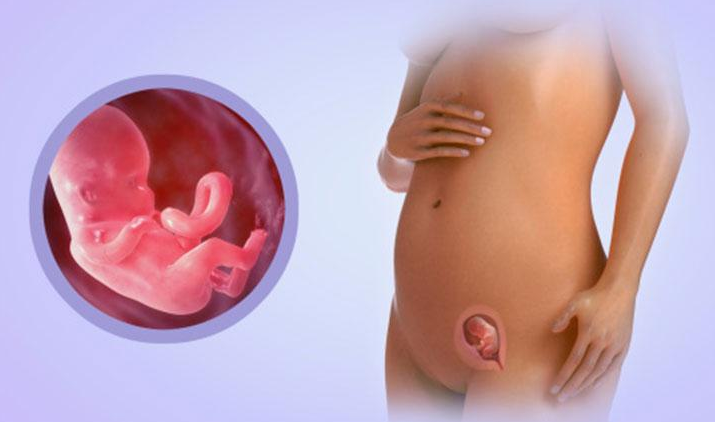

임신 3개월은 임신 초기 1분기 중 마지막 달로, 태아의 주요 장기와 구조가 형성되는 중요한 시기입니다. 이 시기에는 임산부의 몸도 많은 변화를 겪게 되며, 여러 가지 증상이 나타날 수 있습니다.

태아의 발달 단계

임신 3개월 동안 태아는 급격히 성장합니다. 8주가 지나면 얼굴의 특징이 형성되기 시작하고, 10주에는 주요 장기들이 발달합니다. 12주가 되면 태아의 장기가 거의 완전히 형성됩니다. 이 시기에 태아는 약 6~7cm 정도 자라며, 손가락과 발가락도 구분할 수 있게 됩니다.